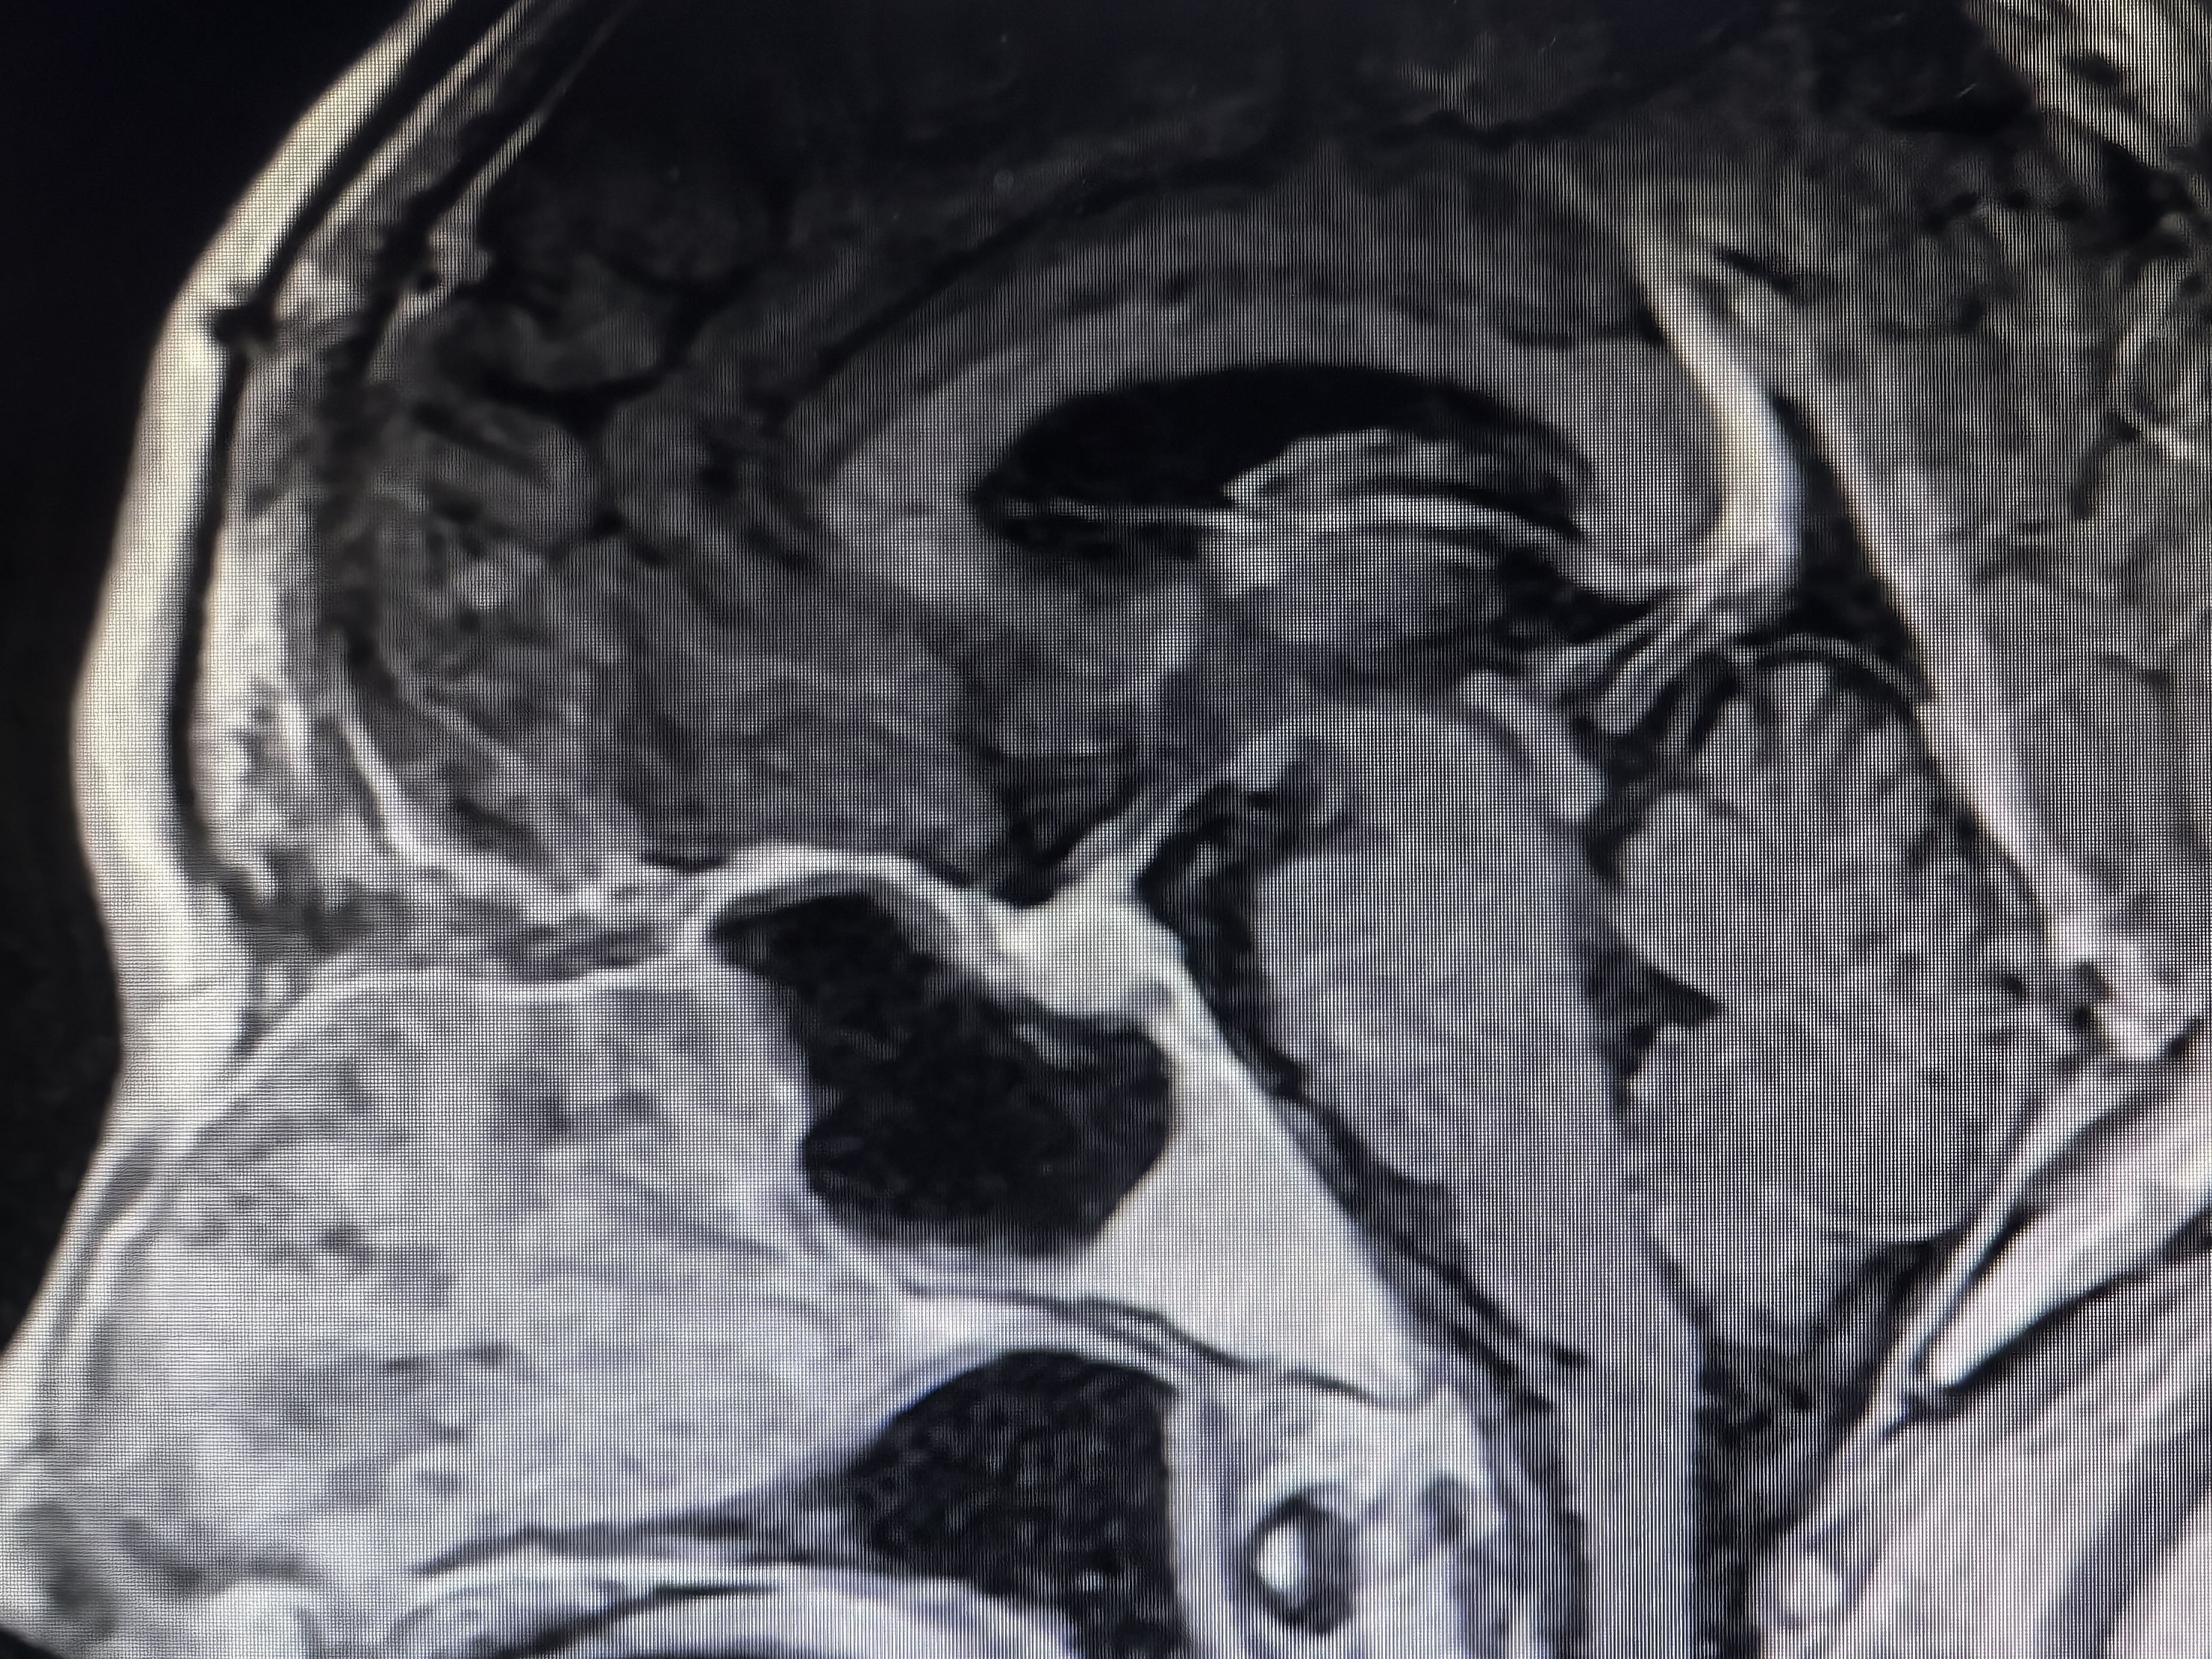

下面展示本病房几例病例:

肿瘤不大,重在规范。